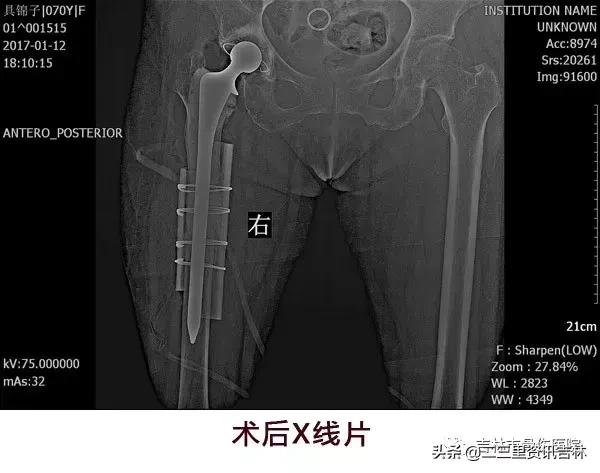

该患于2008年6月因“右股骨颈骨折”在外院行“右侧髋关节置换术”,术后恢复良好,休养至今,于2016年11月30日在自家走路时不慎滑倒摔伤,伤后出现右髋部肿痛,不敢活动,未经处置,在家休养至今未见缓解,现为求系统治疗前来我院就诊,经门诊医生查体拍片后以:“右侧髋关节置换术后假体周围骨折”收入院。

患者入院后给予常规检查,经三级医师查房,临床诊断确诊,查无明显手术禁忌症后在腰硬+全麻麻醉下行“右侧髋关节置换术后假体周围骨折关节翻修术”,术后抗感染、消肿、抗凝、关节功能松动练习等对症治疗,术后患者恢复良好。